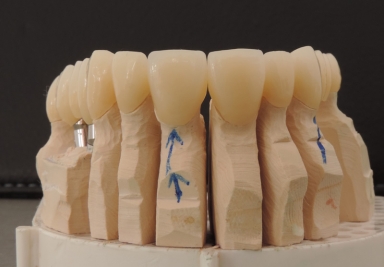

Full maxillary rehabilitation

full ceramic individual crowns in the frontal maxillary area

E-max full ceramic crowns

E-max full ceramic crowns on frontal upper incisors